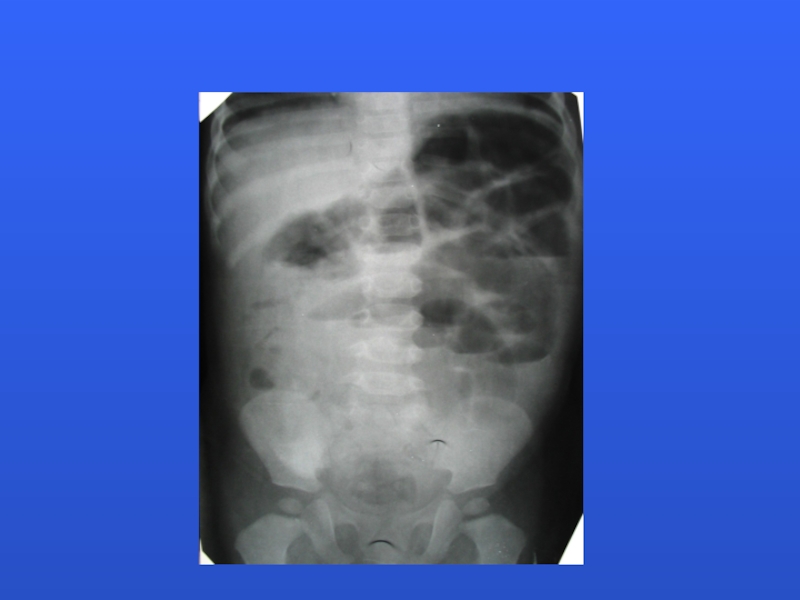

Слайд 20 RADIOGRAPHIC EVALUATION

Plain radiographs (acute abdominal series)

Plain films suggestive in majority,

but cannot rule out diagnosis

PAUCITY OF LUMINAL AIR IN INTESTINAL

SMALL BOWEL DISTENTION, AIR FLUID LEVELS

LUMINAL AIR CUTOFFS (CECUM, TRANSVERSE COLON)

Suggestive clinical symptoms and compatible or nonspecific plain films should undergo evaluation with air or barium enema